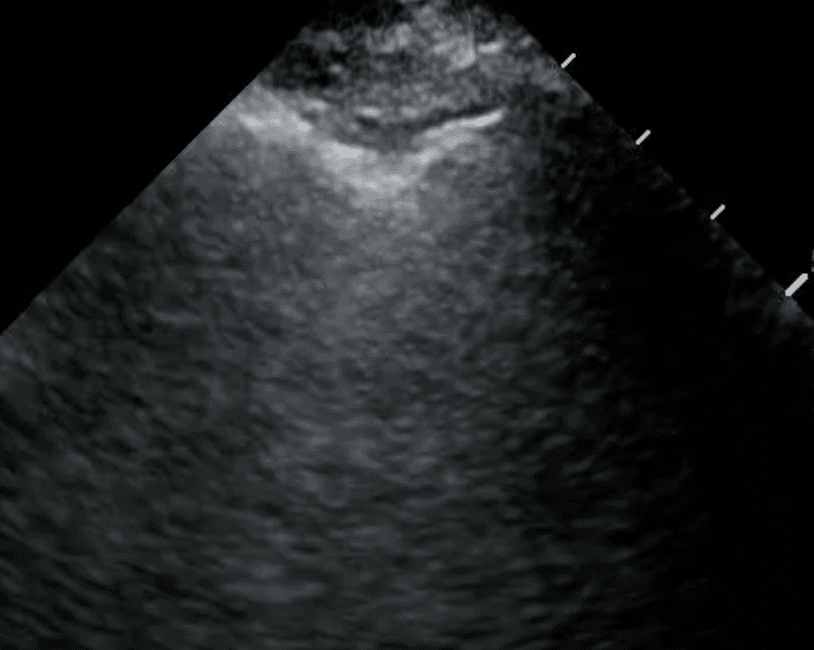

Chronic TB infection can lead to thickening of the pleura, the membrane lining the inside of the chest cavity and covering the lungs. Pleural thickening may be visualized as hyperechoic (bright) bands or irregularities along the pleural line on lung ultrasound (read more here). This finding is often associated with fibrotic changes and can be indicative of prior or active TB infection.